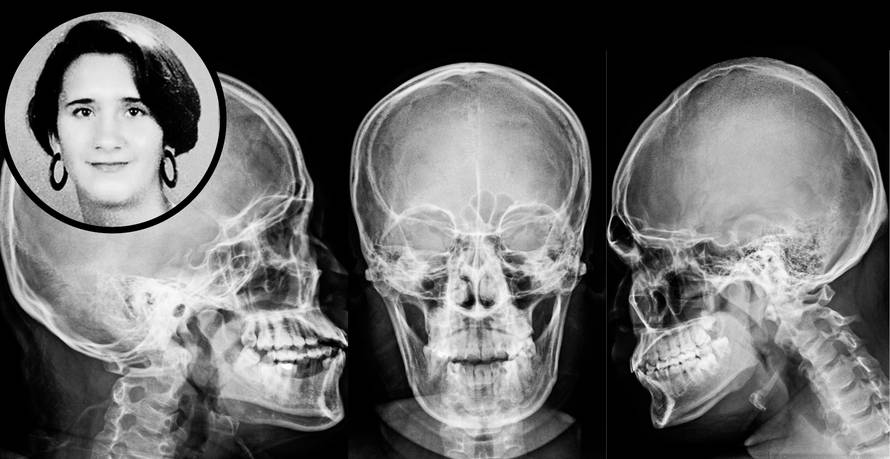

Ubojica je nosio rukavice: Svi udarci koji su ubili Jasminu

Kao uzrok smrti obducentica je navela višestruke prijelome svoda i baze lubanje s ozljedom mozga. Ozljede su nastale udarcima tupo-tvrdim predmetom, i to, najvjerojatnije, dok je žrtva ležala